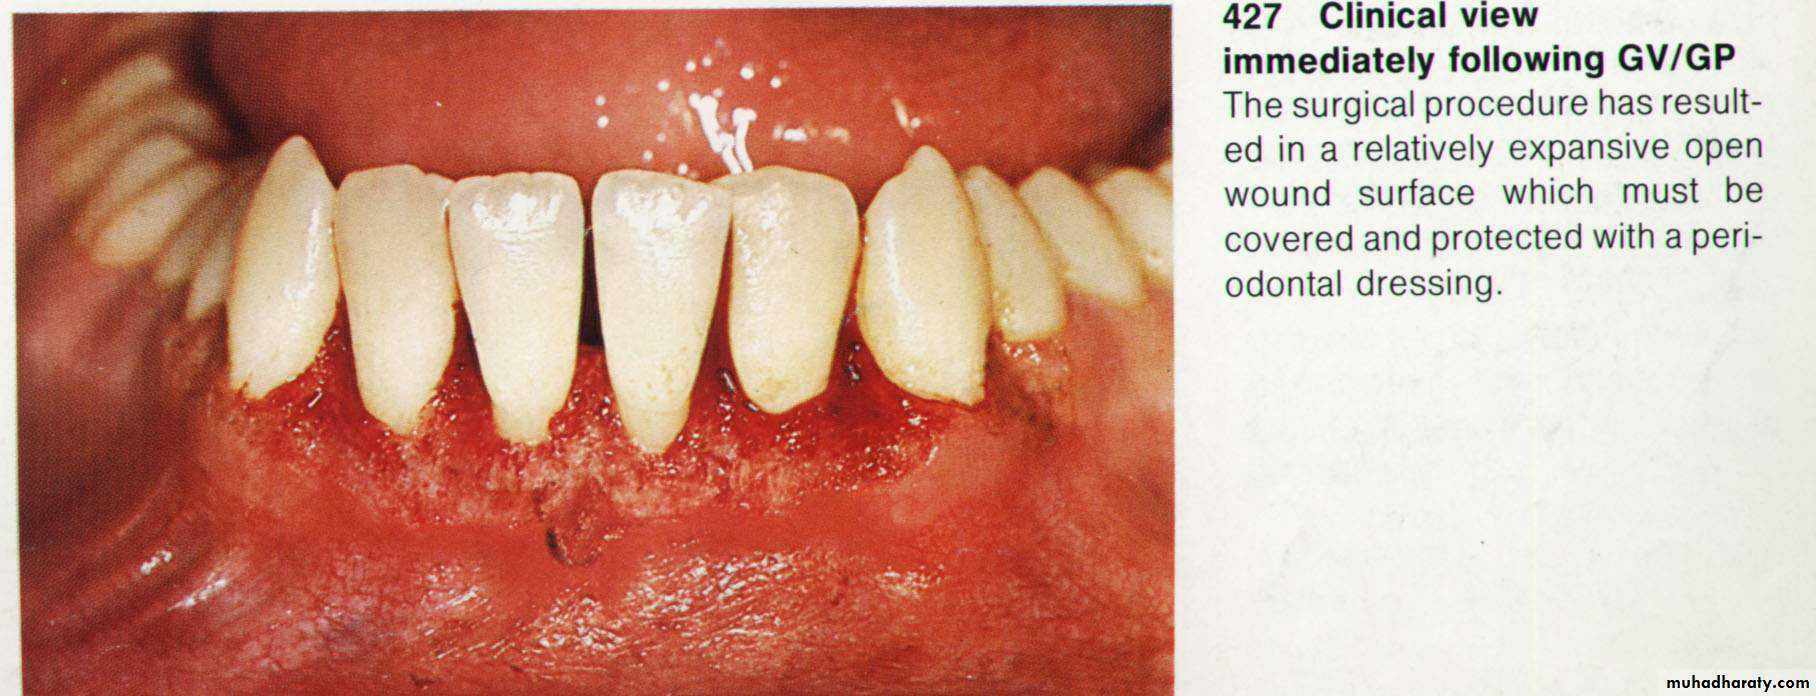

8. Dressing of the wound for (7 – 10 days).